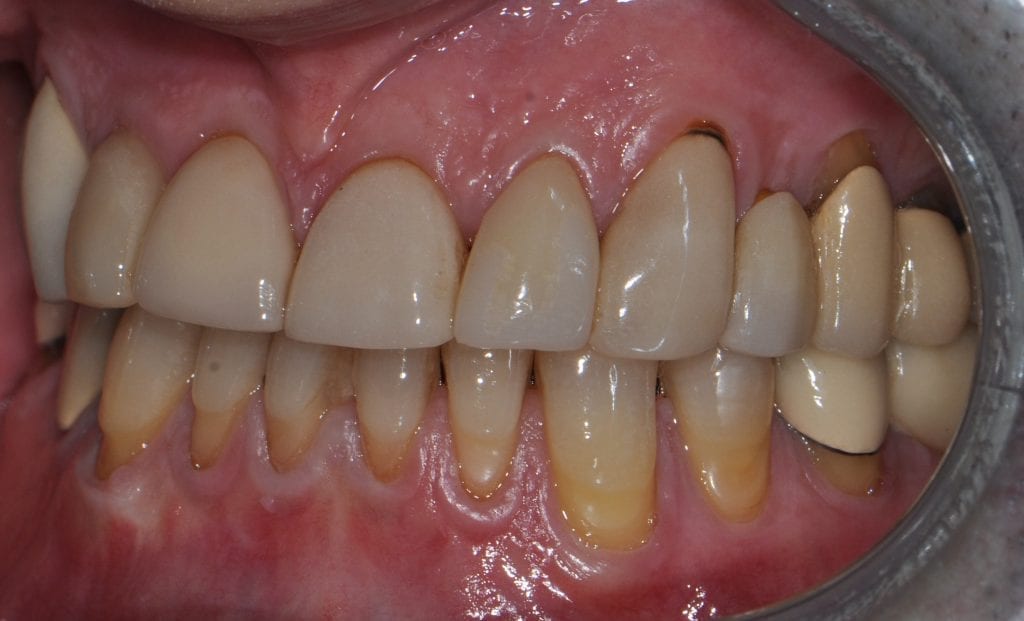

Pre-existing restorations that warranted replacement with an increase in vertical dimension.

Pre-existing restorations that warranted replacement with an increase in vertical dimension. The upper and lower arch were captured with the medit I500 and articulated together with enough clearance to accommodate new restorations and to restore the patient to an ideal tooth position.